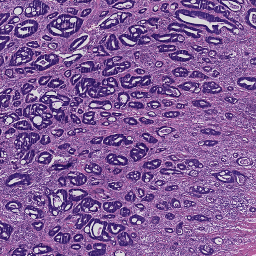

A set of 74 histological slides from 74 patients was prepared from surgically excised rectal carcinomas in patients who had not received neoadjuvant chemotherapy and/or radiotherapy. Slide preparation involved standard fixation of 2m tissue sections and H&E staining. Whole-slide scanning was performed at 200X magnification (pixel resolution = 0.455 m) using a Hamamatsu NanoZoomer 2.0-HT C9600-13 scanner (Herrsching, Germany), which produce 74 gigapixel whole-slide images. Manual annotations of 9 tissue classes were made by an expert using the open source software ASAP555github.com/GeertLitjens/ASAP developed in-house, which included: (i) tumor, (ii) stroma, (iii) necrosis, (iv) muscle, (v) healthy epithelium, (vi) fatty tissue, (vii) lymphocytes, (viii) mucus and (ix) blood cells (see Figure 2). All annotations were successively thoroughly checked by a pathologist and corrections were made when necessary. In the rest of the paper, we refer to this dataset as rectal cancer (RC) data.

A dataset of colorectal cancer images and patches from 10 patients was recently made publicly available [4]. The test dataset consists of two subsets. The first subset contains 5000 patches of 150150 pixel extracted from 10 H&E slides of CRC cases. The patches contain 625 examples of 8 tissue types, namely (i) tumor epithelium, (ii) simple stroma, (iii) complex stroma, (iv) immune cell conglomerates, (v) debris and mucus, (vi) mucosal glands, (vii) adipose tissue, (viii) background. We name this subset as CRCp. The second subset contains 10 tiles of size 50005000 pixel of H&E stained CRC tissue samples, which we call CRCt.

3.1 Rectal cancer tissue classification

We evaluated the performance of the ConvNet on the RC dataset using a 5-fold cross-validation approach. We build each fold selecting 40 WSI for training, 19 for validation and 15 for test, without overlap of patients across datasets. For each fold, the ConvNet was trained with 4000 iterations of stochastic gradient descent with a constant learning rate of 0.0003, the ADAM algorithm for the update of the parameters and categorical cross-entropy as loss function. For each iteration, a mini-batch of 256 patches was built on-the-fly by randomly sampling a balanced amount of patches from each manually annotated class in the training set. Data was augmented by rotating each patch of 90, 180 and 270 degrees, increasing the amount of training patches to approximately 4 million per fold. During training, the performance of the system was monitored by classifying a fixed validation set of 45000 samples (5000 per class). After training, the performance was measured by comparing the label of pixels in the regions manually annotated and the result of the classifier over the 74 WSIs in the RC dataset. An overall 9-class accuracy of 93.8% was obtained. Overall performance of per-class sensitivity and specificity are reported in Figure 3.